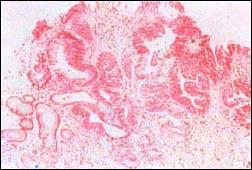

El pólipo tipo III de Nakamura, que en los primeros tiempos en el Japón se denominó por su autor como epitelio atípico, actualmente cobra carta de ciudadanía llamándosele simplemente pólipo tipo III o flat adenoma (este adenoma Fig 6 y foto 14, 15 y 16: la foto 2 es el original presentada por Nakamura.

Foto 14

Foto 15

Foto 16

Las microfotografías 15 y 16, de nuestra casuística, muestran pólipos catalogados como Nakamura III. Presentan una apariencia sesil. histologicamente peculiar con estructura en 2 capas; la capa superior consiste en glándulas displásicas, simulando glándulas de Lieberkuhn, mientras la capa inferior presenta glándulas pilóricas no displásicas y numerosos quistes.